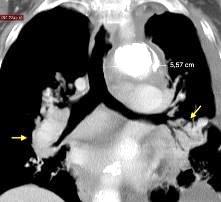

Ganglios retroperitoneales (flechas negras)

germinales del testículo izquierdo Nódulos pulmonares múltiples. (flechas verdes). Ganglios paratraqueales. (flechas amarillas). Dudoso ensanchamiento retrocrural (flechas negras)

Panda A et al. “Straddling Across Boundaries”. Thoracoabdominal Lesions: Spectrum and Pattern Approach. Curr Probl Diagn Radiol, 2015